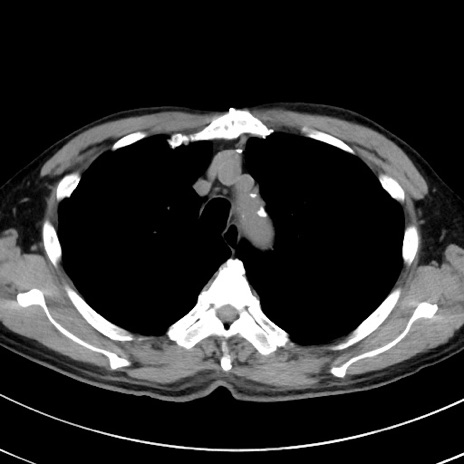

冠状断像

症例38(横断像)

【症例】70歳代 男性

【主訴】腹痛・嘔吐

【現病歴】昨晩より、嘔吐・腹痛あり。今朝になっても嘔吐あり。来院。

【既往歴】心臓バイパス手術、開腹胆摘、腸閉塞

【身体所見】BP 107/71mmHg、HR 116/min、腹部:平坦、軟、下腹部に軽度圧痛あり。反跳痛なし。

【データ】WBC 15100、CRP 0.32